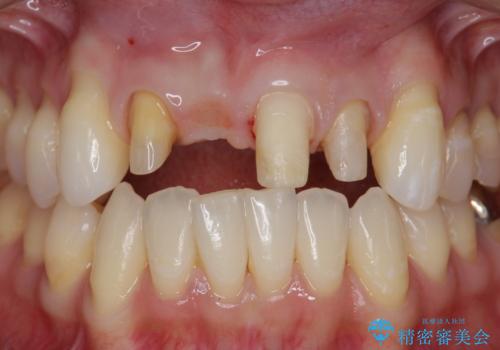

吸収し喪失した前歯、ブリッジによる審美性の回復

- 前医に前歯の吸収による抜歯の必要性を伝えられ、前歯の審美的な改善・治療を求めて来院されました。

CT撮影を行った結果、右上前歯は吸収が進み抜歯が必要な状態です、

抜歯をせず放置すると、より吸収が進み臨在する歯にも悪影響を及ぼしてしまう可能性が考えられます。

上顎4前歯は、根管治療の既往があり、虫歯も見られたことからブリッジによる治療で審美性の回復を行うとともに臨在歯の虫歯もセラミック治療を行っていきます。